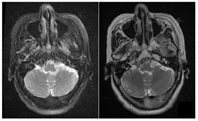

生命体征:体温36.5℃,脉搏70次/min,呼吸18次/min,血压120/80 mmHg。入院MCV测定(用脉冲电流分别刺激左右面神经,于左右眼轮匝肌及口角匝肌记录),左侧记录的神经电位波幅均降低(眼轮匝肌:左3.3 mV,右8.3 mV;口轮匝肌:左1.1 mV,右3.8 mV),提示左侧面神经病变、异常运动传导速度。神经重复刺激结果未见异常。颞骨高分辨CT示左侧面神经管较对侧增宽,局部膨大,最宽径约4.6 mm,双侧乳突气化稍差,左侧乳突黏膜略增厚(图1、图2)。